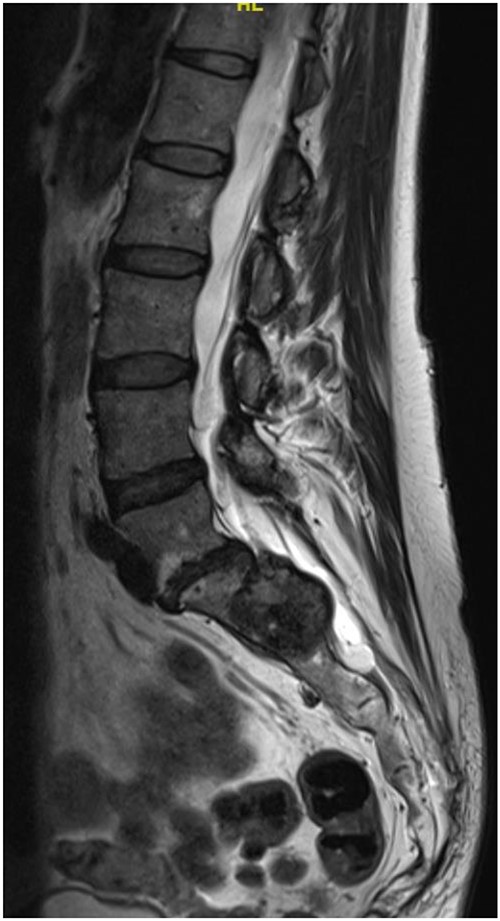

At a further review (November 2018), a contrast MRI scan was requested at a follow-up in early November for 3 months post-index scan. At the follow-up, a left S1/S2 sacral tumour (most possibly schwannoma) with no change in the size was diagnosed. Repeat physical examination confirmed status quo on the neurological deficit. The decision was to review after 12 months as the patient remained stable.

Reviews in July 2019 (with an MRI scan in December 2019) and December 2020 confirmed no neurological deterioration but some increased back and leg pain when standing for some time. A repeat MRI scan confirmed an increase in the size of the lesion (Figs 1 and 2). A biopsy was arranged with a plan for a follow-up surgery. Results of the CT-guided biopsy indicated a diagnosis of metastatic malignant melanoma. Discussions with the patient did not localise any skin lesion responsible for the metastatic deposit, an F18-fluorodeoxyglucose positron emission tomography (18F-FDG PET/CT) scan and a conventional computed axial tomography (CT) scan was organised (April 2021), which revealed sacral destruction and no other deposits in the chest, abdomen and pelvis (Figs 3 and 4). Our patient had a reported SUV of 3.6, indicating a malignant lesion that was then confirmed operatively.